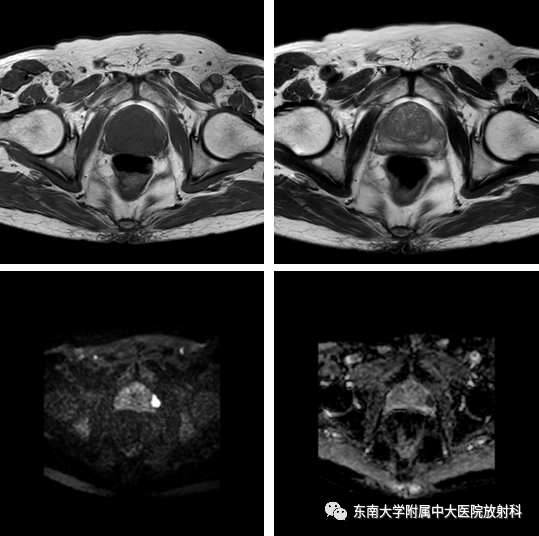

•患者1年前体检发现PSA升高,TPSA 19.793 ng/ml,无肉眼血尿,无尿频尿急尿痛,无畏寒发热。6天后复查TPSA 15.40 ng/ml,盆腔MR平扫示:左外周带3点钟方向异常信号结节,PI-RADS 4 级,遂行超声引导下前列腺穿刺活检,病理提示:正常前列腺组织。后患者于2019-10-24至我院复查TPSA 25.92 ng/ml

2019-10-26影像学表现